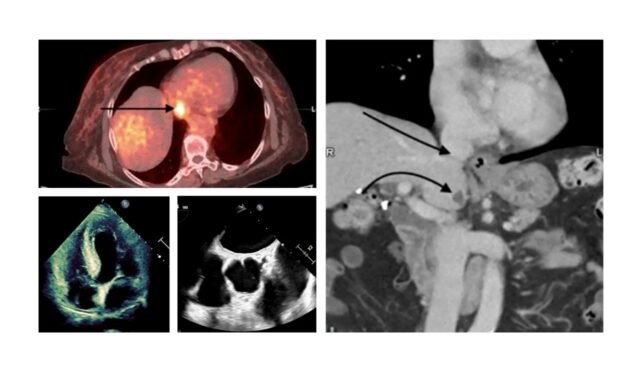

Busra Cangut博士的細節“ 18F-FDG掃描(類型的葡萄糖放射性)PET/CT可以確定癌症的階段,顯示出右走廊的嚴重活性,類似於傑出的組織。”她的癌症評估中的一部分揭示了她的右大廳的重要活動。出乎意料的是,最初引入了可能的危險質量。這種相關的觀察結果導致了深度評估,這解釋了它是一個獨特的crista末端,這是心跳結構的一般變化。

“ crista末端位於Etrium的右側,沿著兩個重要靜脈(Vena Cava)之間的側壁延伸,這比Crista末端中的某些正常F-18 FDG活動不如一些。在該腫瘤的分析中可以異常指定它可能會表現出對癌症的疾病的疾病,這可能是對癌症的疾病的差異,這一點是對癌症的範圍。標準心跳結構的生理吸收和有毒變化,以防止錯誤的解釋。